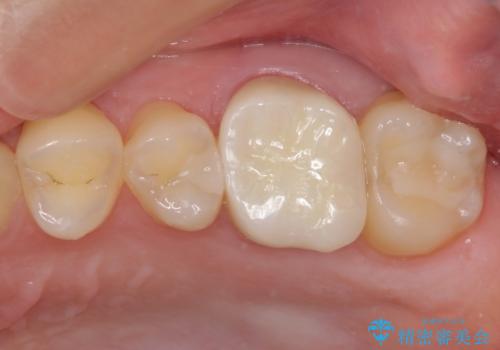

口を開けたときに見えてしまう部分はセラミックインレーやジルコニアクラウンに、目立たない部分はゴールドインレーにてむし歯治療を行うこととしました。

機能面を優先すると、PGAインレー(ゴールドインレー)による修復治療やPGAクラウンによる補綴治療が望ましいのですが、笑ったときに見えている銀歯がどうしても気なってしまうとのことで、目立ってしまう奥歯はセラミックインレーやセラミッククラウンを装着することとしました。

見た目を気にすることなくむし歯治療を行うことができ、患者様に大変満足していただきました。